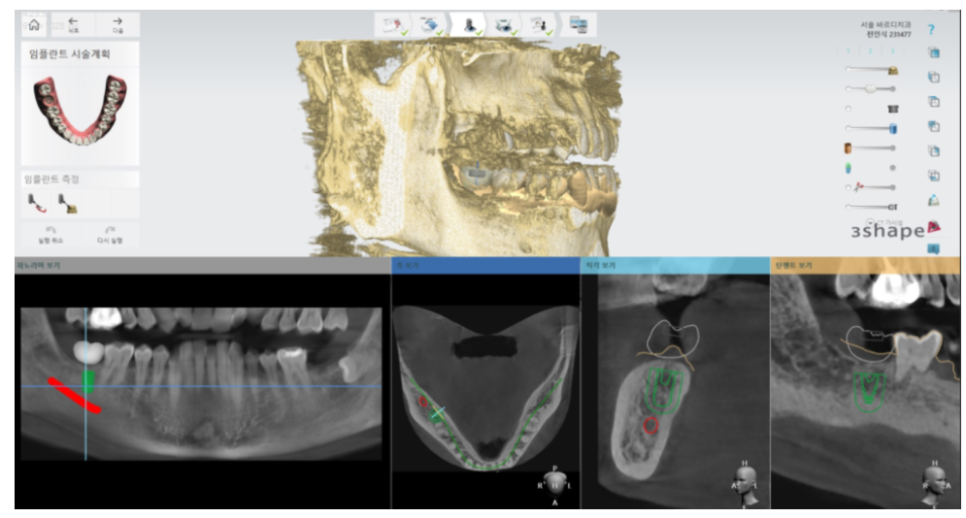

먼저 구강 상태를 정확히 파악하기 위해

x-ray 및 ct 촬영을 시행합니다.

이때 미리 네비게이션 임플란트 수술을 위한 준비를 하기도 하고요.

두번째로 네비게이션 임플란트 기술을 활용하는겁니다.

보다 정확하고 빠르게 식립!

최신 기술을 적극 활용하는겁니다.